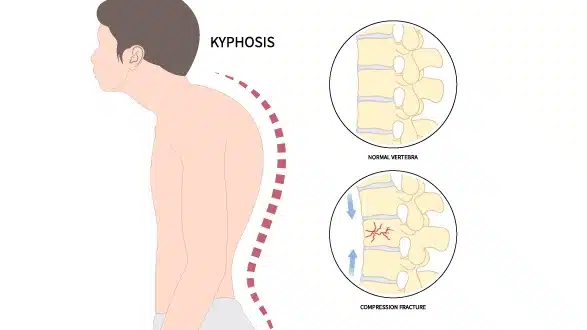

رابعًا: ما هو تقوس الظهر (الحداب)؟

تقوس الظهر هو انحناء للأمام في الجزء العلوي من العمود الفقري. في الحقيقة، هذا الانحناء طبيعي بدرجة معينة، لكن المشكلة تظهر عندما يزيد عن الحد الطبيعي.

📌 في الحالات الشديدة، قد يبدو الظهر:

- مستديرًا بشكل واضح

- مع ميل الرأس للأمام

- وانحناء في الكتفين

👉 وبالتالي، قد يؤثر على الشكل العام والثقة بالنفس.

سابعًا: هل اعوجاج العمود الفقري وتقوس الظهر خطير؟

في معظم الحالات، تكون الحالتان بسيطتين ولا تسببان مشاكل خطيرة. ولكن:

❗ في الحالات الشديدة:

- قد يحدث ألم في الظهر

- قد يتأثر التنفس

- قد تتأثر الحركة والنشاط اليومي